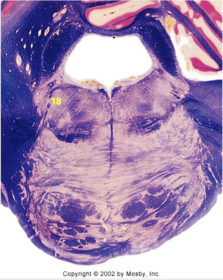

| Abducens root fibers | |

| Longitudinal pontine fibers (corticospinal tract) | |

| Transverse pontine fibers (dark fibers) | |

| Pontine nuclei (pale) | |

| Medial lemniscus | |

| ALS | |

| Trapezoid body | |

| Ventral trigeminothalamic tract | |

| Superior olive | |

| Central tegmental tract | |

| Facial nerve root fibers - descending | |

| Facial motor nucleus | |

| Interposed nuclei | |

| Medial longitudinal fasciculus | |

| Facial nerve root - internal genu | |

| Abducens nucleus | |

| Lateral vestibular nucleus | |

| Superior vestibular nucleus | |

| Inferior cerebellar peduncle | |

| Superior cerebellar peduncle | |

| Dentate nucleus | |

| Fastigial nucleus | |

| Anterior spinocerebellar tract | |

| Spinal nucleus of V | |

| Spinal tract of V | |

| Middle cerebellar peduncle | |